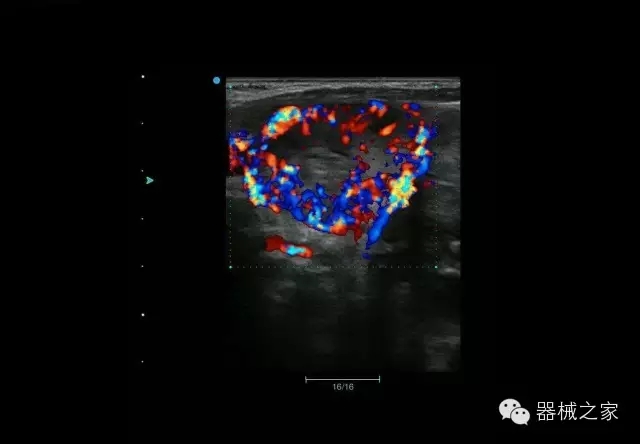

臨床圖片賞析

結(jié)甲